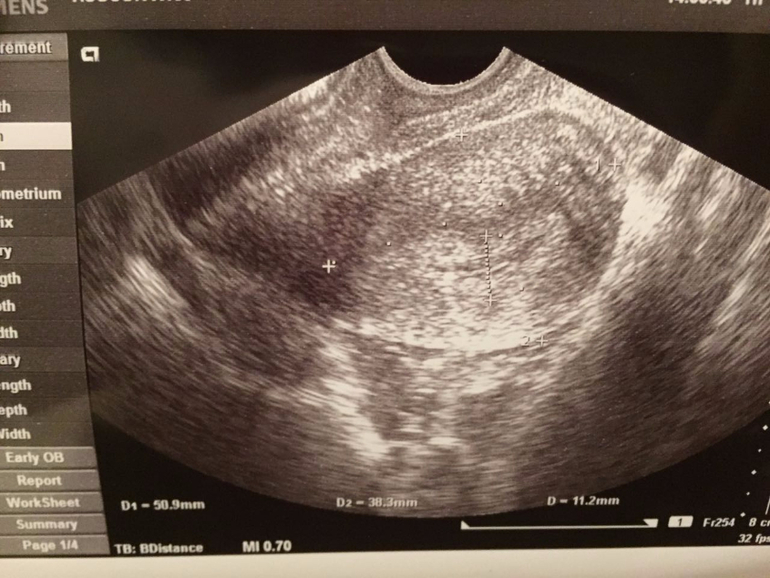

Задержка.Киста ЖТ.

Задержка М и нет БПосмотрите пожалуйста фотки,может кто то что то понимает.

Последний раз месячные были 30 января.Тесты пустые.

На узи сказали киста ЖТ,больше ничего не сказали.К врачу только на следующей неделе,а мне не дотерпеть!!Что мне делать?!?! Или чего наоборот не делать?!Помогите!